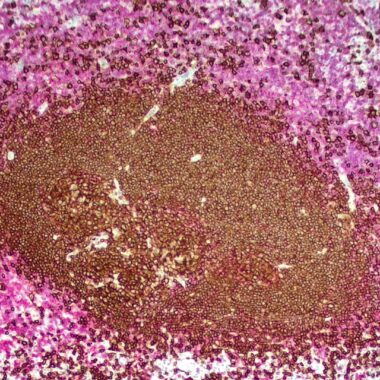

Background Zeta s T/B Cell Cocktail – Dual Stain. Zeta s T/B Cell Cocktail is a dual stain recombinant antibody cocktail that provides dual expression of CD3 and CD20, which is used by pathologists to evaluate lymphoid populations in tissue sections. It allows for the simultaneous identification and spatial assessment of T cells (CD3⁺) and B cells (CD20⁺) , which is critical in diagnosing and classifying a wide range of hematolymphoid and inflammatory conditions. CD3 is a pan-T-cell marker found on all mature T lymphocytes (membrane and cytoplasmic expression). The recombinant antibody ZR414 recognizes the epsilon chain of CD3, which consists of five different polypeptide chains (designated as gamma, delta, epsilon, zeta, and eta). The CD3 antigen is a highly specific marker for T cells and has been reported expressed by most T cell neoplasms. CD20 is B-cell marker expressed on mature B lymphocytes, but not plasma cells. CD20 is a non-Ig differentiation antigen of B cells and the expression of CD20 is restricted to normal and neoplastic B cells, being absent from all other leukocytes and tissues. CD20 is the most specific B-cell marker used in paraffin immunohistochemistry. Clinically, Zeta s T/B Cell Cocktail can help differentiates between B-cell and T-cell lymphomas, which have distinct prognoses and treatments and help identify mixed or composite lymphomas and detect aberrant marker loss or co-expression. Additionally, the T/B Cell Cocktail can support confirmation of monoclonality vs. polyclonal reactive infiltrates: (1) Reactive contains mixed CD3⁺ and CD20⁺ cells and (2) Lymphoma has a dominant population of one cell type. In solid organ pathology (e.g., colon, breast, skin) , the T/B Cell Cocktail can assess, Tumor-infiltrating lymphocytes (TILs) , Chronic inflammation (e.g., autoimmune, viral) , and Immune response patterns in transplant rejection. Zeta s T/B Cell Cocktail combines L26 (red) and ZR414 (brown) and uses two different chromogens to allow distinct visual separation on a single slide. Zeta s DUAL STAIN products provide more information from limited tissues, by seeing two related markers on the same slide while also allowing pathologists to see cellular localization and interaction within the tumor environment. Zeta uses one mouse and one rabbit recombinant monoclonal in each cocktail to allow for differential color results. Zeta Corporation is a leader in recombinant monoclonal IVD antibodies for immunohistochemistry (IHC) offering 400+ tumor and tissue specific relevant products developed by a pathologist for pathologists. Visit Precision Recombinant Antibodies – IVD Antibodies – About Zeta Corporation (zeta-corp.com) to learn more about Zeta Corporation.